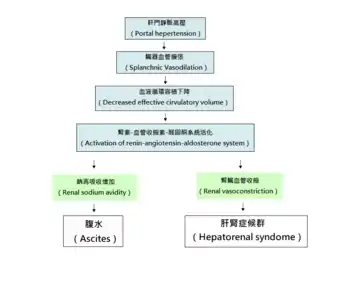

肝肾综合征發生时出现的肾衰竭是肾血管紧张度发生异常所导致的[2],目前普遍认为,一些肝脏疾病所产生的因子引起内脏血管舒张(主要是由门脉高压所导致的肠循环血管舒张)和肾血管床缩窄,從而導致了腎衰竭[4][12]。体内的氮氧化物(如NO)[13]和前列腺素[14]等可导致血管舒张的因子很可能介导了肝硬化时内脏血管的舒张。内脏血管舒张會刺激肾小球近血管球体感受器,导致肾素分泌和肾素-血管紧张素系统活化,進而使全身循環系统收缩,尤其是肾血管的收缩[2]。然而这依然不能抵消内脏血管舒张造成的影响,因此,肾循环处于持续的低灌注状态,這又加重了肾血管的收缩,导致肾前性肾衰竭[12]。

基于此理论所做的定量实验显示,在肝肾综合征发生时,全身的外周循环阻力降低,然而股动脉流量占心输出量的百分比增高,肾动脉流量則降低,顯示内脏血管舒张累及肾脏造成肾衰竭[15]。许多作用於血管的因子可能介导了这种全身性的血流动力学变化,包括心房钠尿肽[16]、前列環素、血栓素A2[17]和内毒素[4]。另外研究发现,用抵抗血管舒张的药物(如鳥氨酸加壓素[16]、特利加压素[18])治疗可以改善肝肾综合征患者的肾小球滤过率,进一步为肝肾综合征的内脏血管舒张理論提供了证据[16]。

肝門脈系統分流的結果也支持內臟血管舒張理論。肝肾综合征患者在進行分流降低門脈壓力之後,腎功能有些微的改善[19]。該手術雖然能夠有效降低腹水及肝肾综合征的發生率,但同時也會增加腦病變的風險,目前該手術對於死亡率是否有影響尚無定論[20]。

肾血流低灌注理论中包含了肾素-血管紧张素系统的激活,而醛固酮可以与肾脏远曲小管上的盐皮质激素受体结合,造成钠的重吸收增加[8][12],这是肝硬化腹水的发病机制中的关键过程。有假說認為腹水和肝腎症候群同屬一個疾病光譜,皆由臟器血管擴張所致[8]。